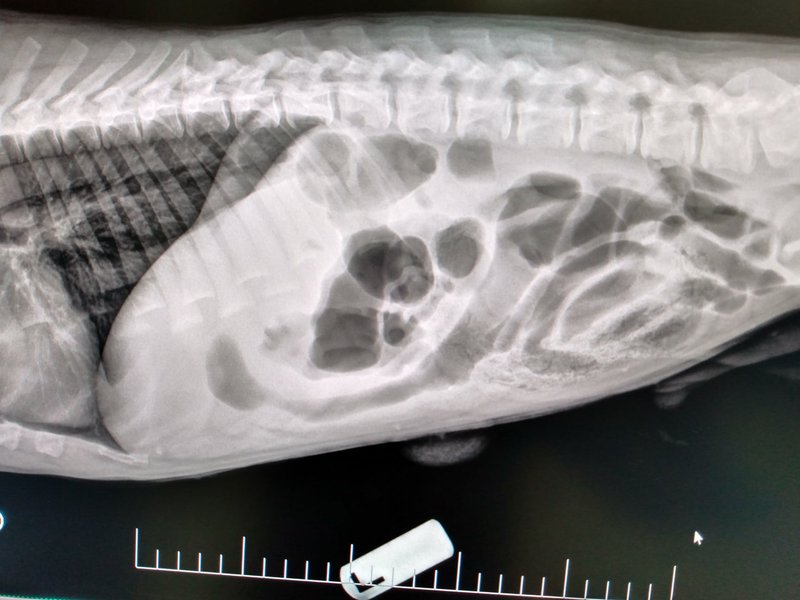

As a pet parent, you may notice when something “isn’t quite right” with your pet, but determining the cause is not always straightforward. That is where diagnostic testing comes in. At Uptown Animal Hospital, our veterinary team is committed to providing a complete picture of your pets health through advanced laboratory and diagnostic services, helping us make informed decisions and deliver the best possible care.

Knowing when your pet is unwell is one of the most challenging parts of pet care. Annual blood and lab tests help determine a normal baseline for your pet's health. Monitoring these results over time allows us to diagnose problems early, increasing the likelihood of timely intervention and recovery so your pet can live their best life.